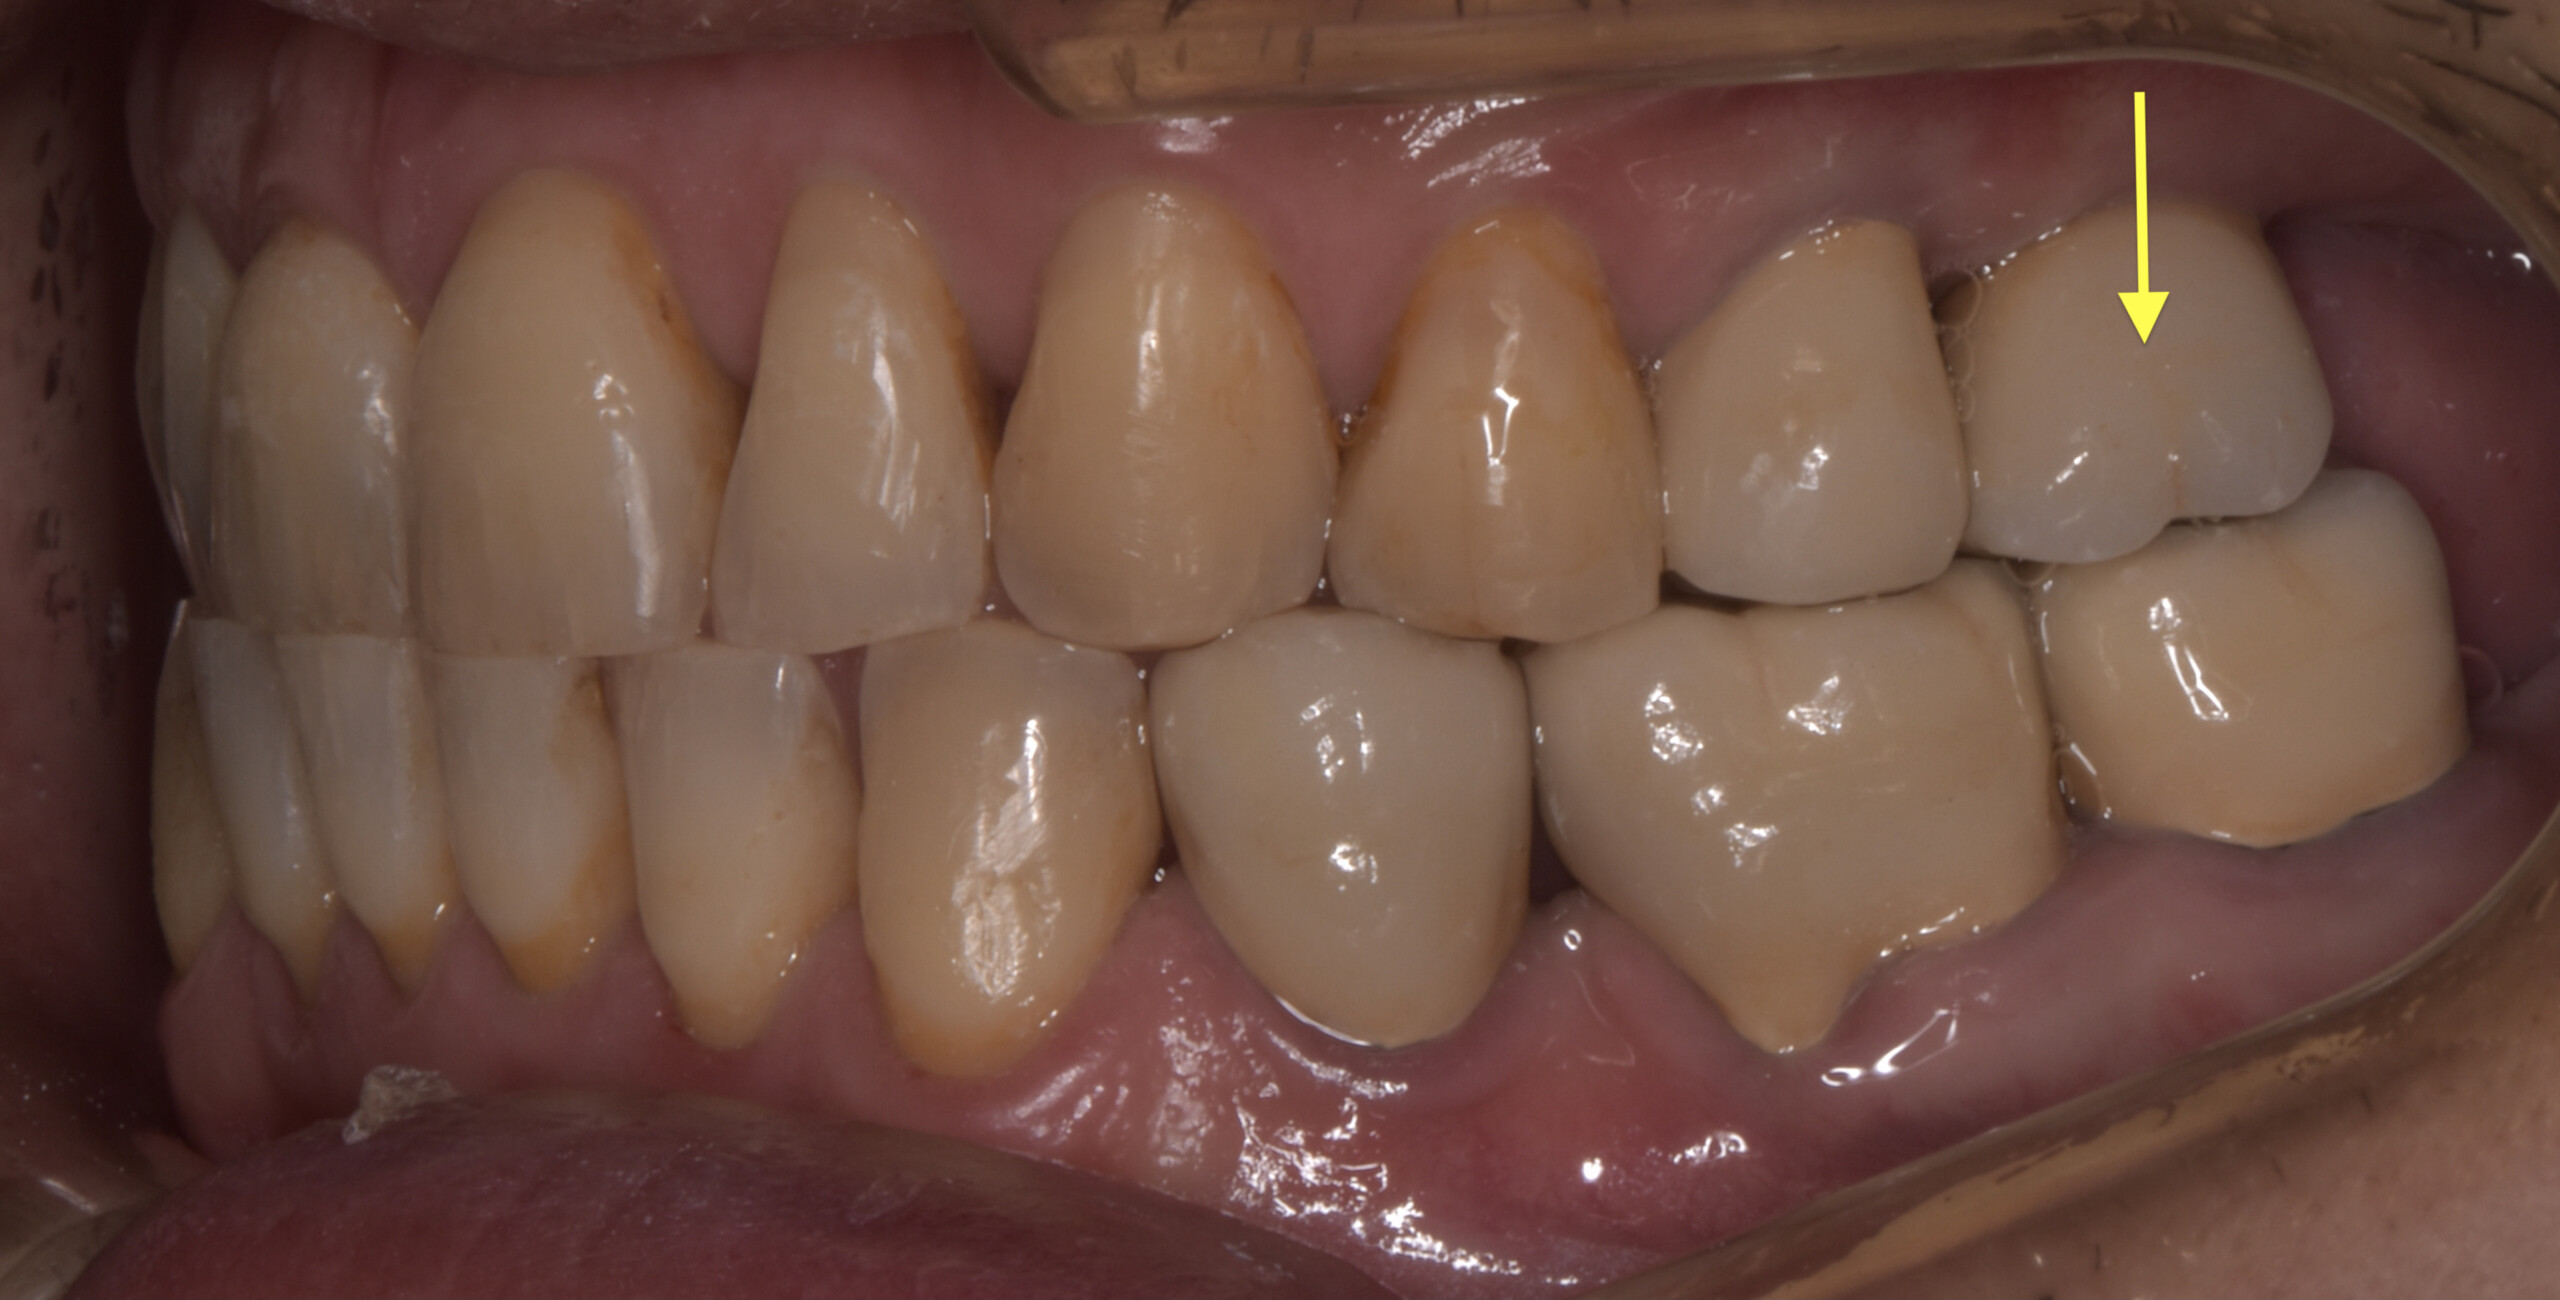

治療前画像の黄色い矢印の歯が非常に強く当たっていることが、デジタルによる画像からもわかります。そこでその歯を抜歯をすることで顎関節の症状が無くなるのではないか?という予測を立てました。

同時にこの歯は大きな虫歯が全く治療されていない事、また破折を起こしていたため結果的に抜歯という選択肢は、虫歯治療という側面からも整合性をもっています。